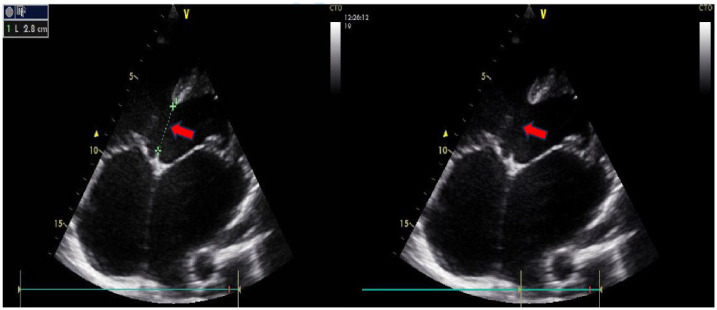

大多数室间隔缺损患者都能活到成年,这就为肺动脉高压等其他并发症的逐渐发展留出了时间。如果伴有其他心脏疾病(如瓣膜性心脏病),也会导致肺动脉高压的发生,那么肺动脉高压可能会加重。由于肺动脉高压的这些不同病因具有不同的机制,它们的并存会使患者的治疗变得复杂。我们介绍了一名患有室间隔缺损和风湿性二尖瓣疾病的 26 岁男性患者,他患上了严重的肺动脉高压,并与心房颤动和后来的心脏性猝死并发。

Most individuals with ventricular septal defect survive to adulthood which allows time for other complications such as pulmonary arterial hypertension to gradually develop over a period of time. When there are other associated cardiac conditions that also contribute to the development of pulmonary hypertension such as valvular heart disease, the pulmonary hypertension may be exaggerated. Because these different etiologies of the pulmonary hypertension have different mechanisms, their coexistence can complicate patient management. We present a 26-year-old man with a large ventricular septal defect and rheumatic mitral valve disease who developed severe pulmonary hypertension that became complicated by atrial fibrillation and later sudden cardiac death.